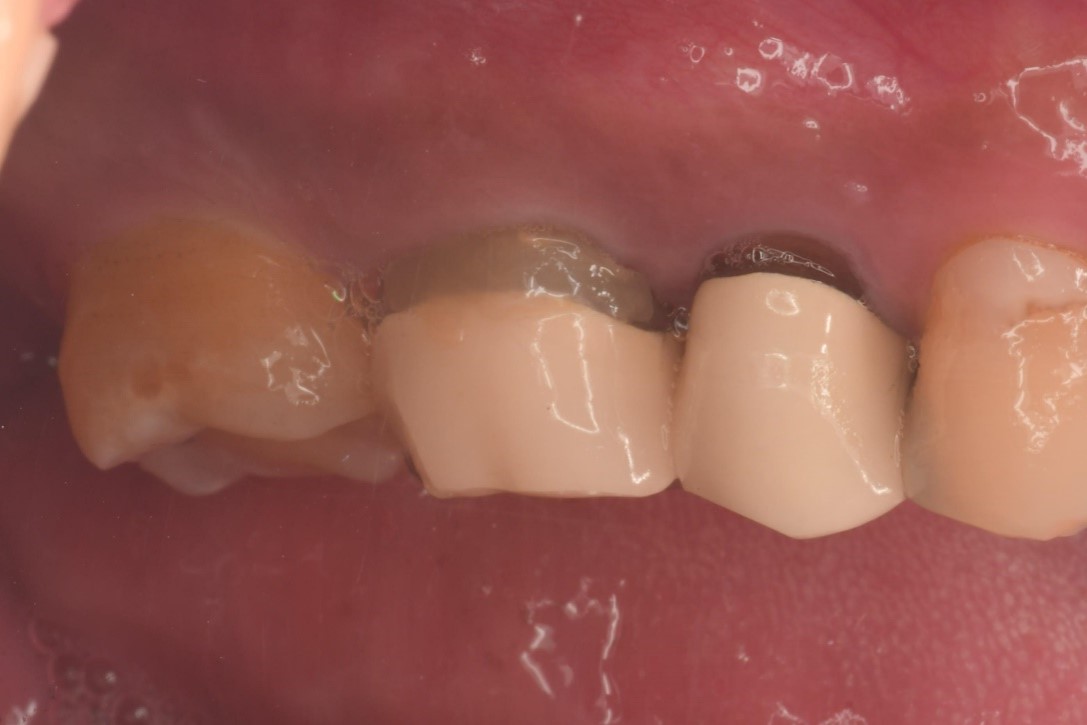

牙髓-牙周-膺復合併症-根尖病變-#16

根管治療

牙髓/牙周/膺復合併症